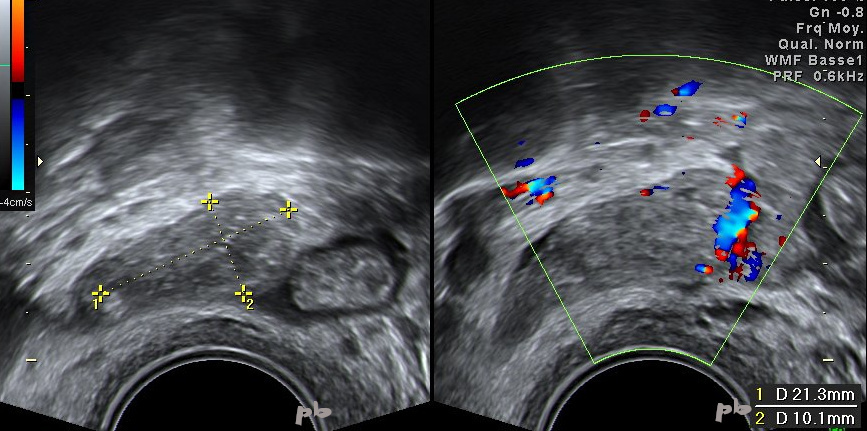

25 – EP

Miscarriage 15 days ago. Metrorrhagia. Stagnation of β-HCG levels at 250 IU.

Evidence of a small ectopic pregnancy measuring 21 x 10 mm (longitudinal section) between crosses.

Digestive segment on the right in the image.

26 – EP (same patient as 25)

Evidence of a small ectopic pregnancy (►). Transverse section.

Low vascularization at the periphery.